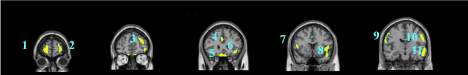

Figure 1A.  Transverse slices showing the deficits of autistics subjects when compared to healthy controls using SPM (p < 0.001 FDR Correction):  1) Occipital Superior Left; 2) Post Central Right; 3) Cingulum Anterior Right; 4) Precentral Left; 5) Cingulum Mid Right; 6) Temporal Mid Right; 7) Angular Superior Right; 8) Temporal Superior Left; 9) Frontal  Superior Left; 10) Frontal Inferior Triangularis Right; 11) Frontal Superior Orbital Left;  12) Temporal Mid Left;  13) Rolandic Operculum Right; 14) Frontal Inferior Right; 15) Frontal Inferior Left; 16) Temporal  Mid Left; 17) Frontal Inferior Orbital Left; 18) Temporal Inferior Left.

Figure 1B.  Coronal slices showing the deficits of autistics subjects when compared to healthy controls using SPM (p < 0.001 FDR Correction):  1) Frontal Superior right; 2) Frontal Superior left; 3) Frontal Mid Left;  4) Cingulum Anterior Right; 5) Frontal Inferior Orbital Right and Left;  6) Temporal Inferior Left; 7) Rolandic Operculum Right; 8) Temporal  Superior Left; 9) Occipital Mid Right and Angularis Right; 10) Left Angularis and Occipital Mid Left;  11) Temporal Inferior Left.

Figure 1C.  Sagittal slices showing the deficits of autistics subjects when compared to healthy controls using SPM (p < 0.001 FDR Correction). 1) Post and Precentral Right; 2) Right Triangularis; 3) Angular Gyrus Right; 4) Left inferior Orbital Cortex; 5) Cingulum Left; 6) Triangularis Left; 7) Frontal Cortex Mid and inferior Left); 8) Temporal Inferior Anterior Cortex left; 9) Precentral  Left; 10) Post Central Left;  11) Occipital Left.